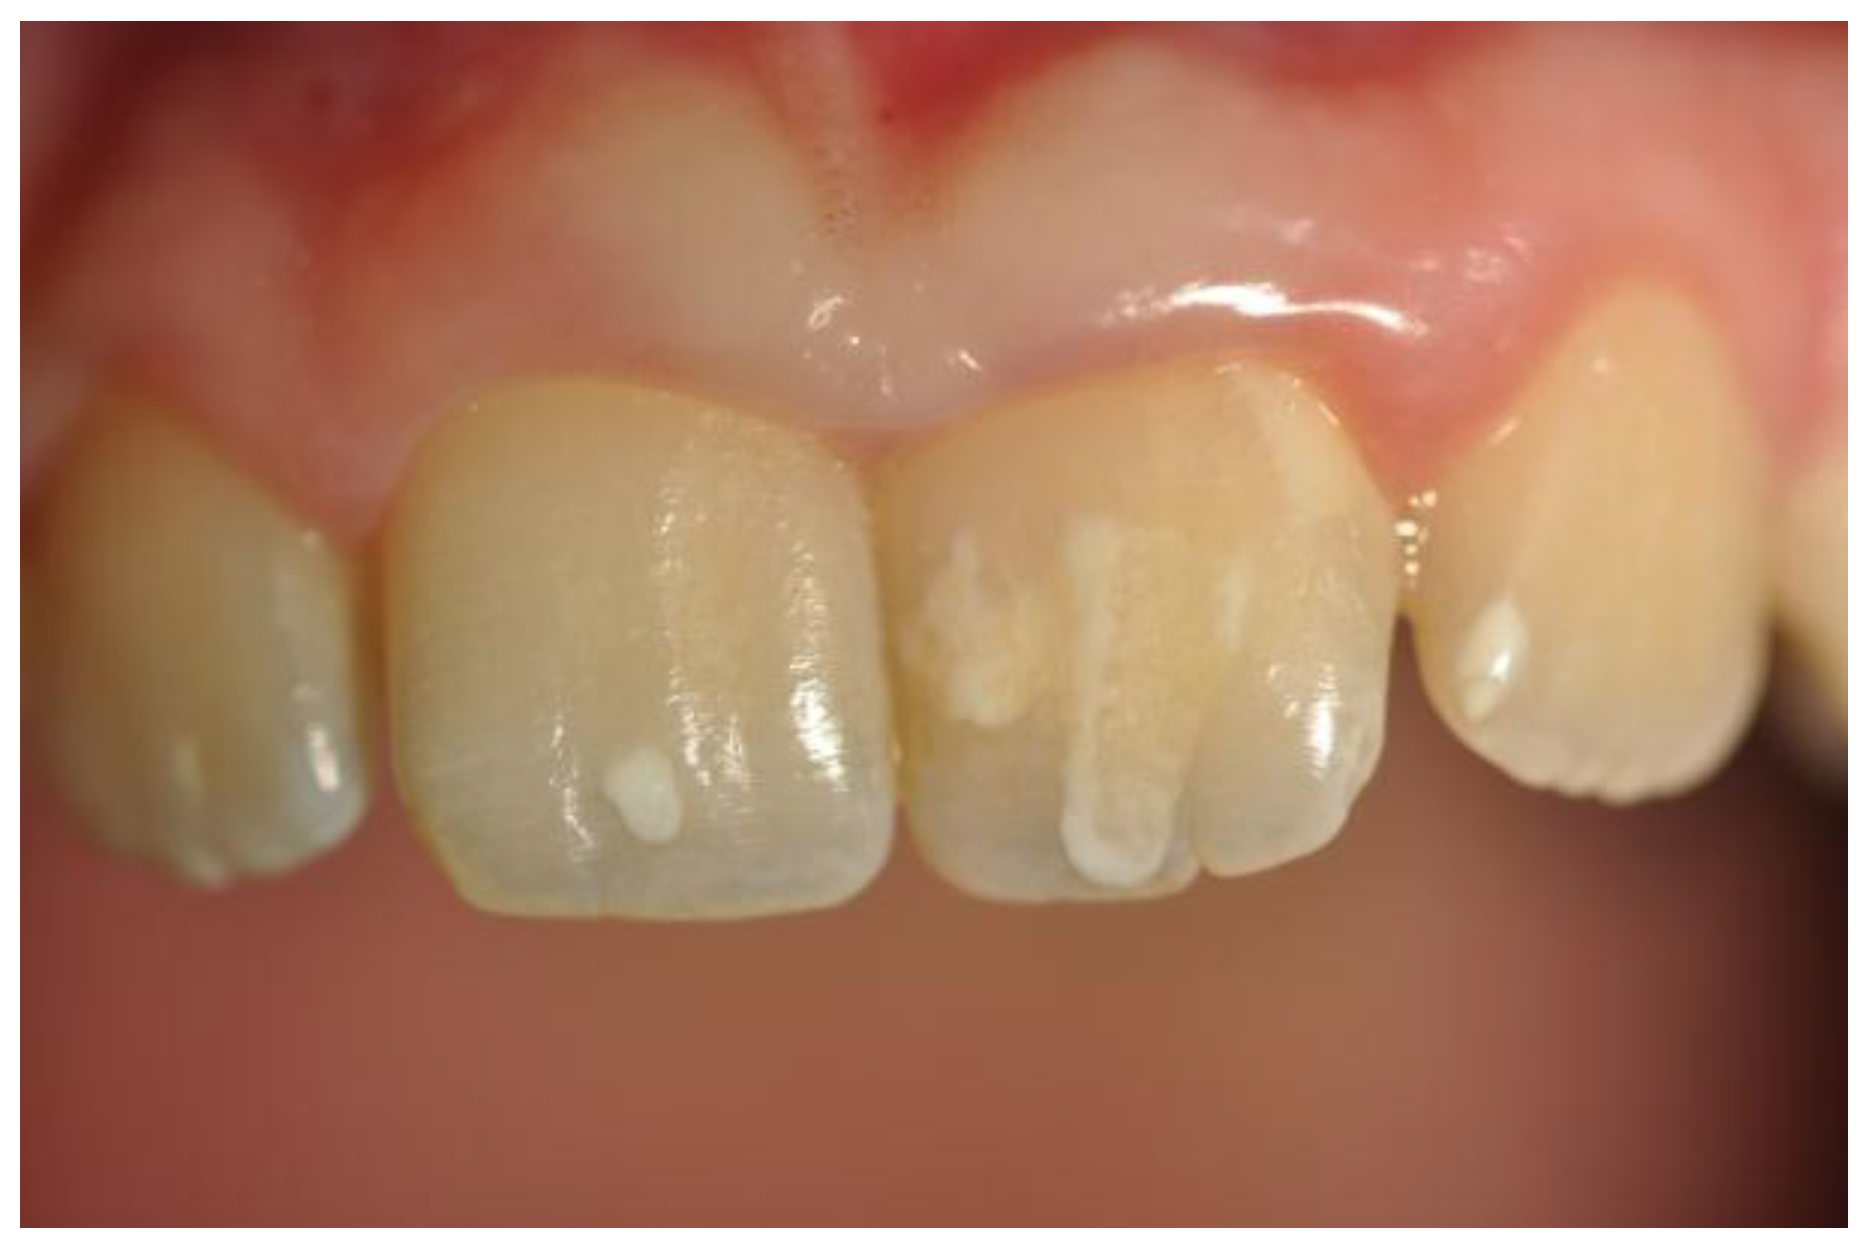

Following this classification we observed: Score 1 (loss of enamel characteristics) in four CD patients, Score 2 (exposing dentine for less than one-third of surface) in three, Score 3 (exposing dentine for more than one-third of surface) in two (Figure 3). In the control group, we only found three patients with tooth wear, all classified as Score 1.

Figure 3. A case of tooth wear in a celiac disease (CD) patient (Score 3).